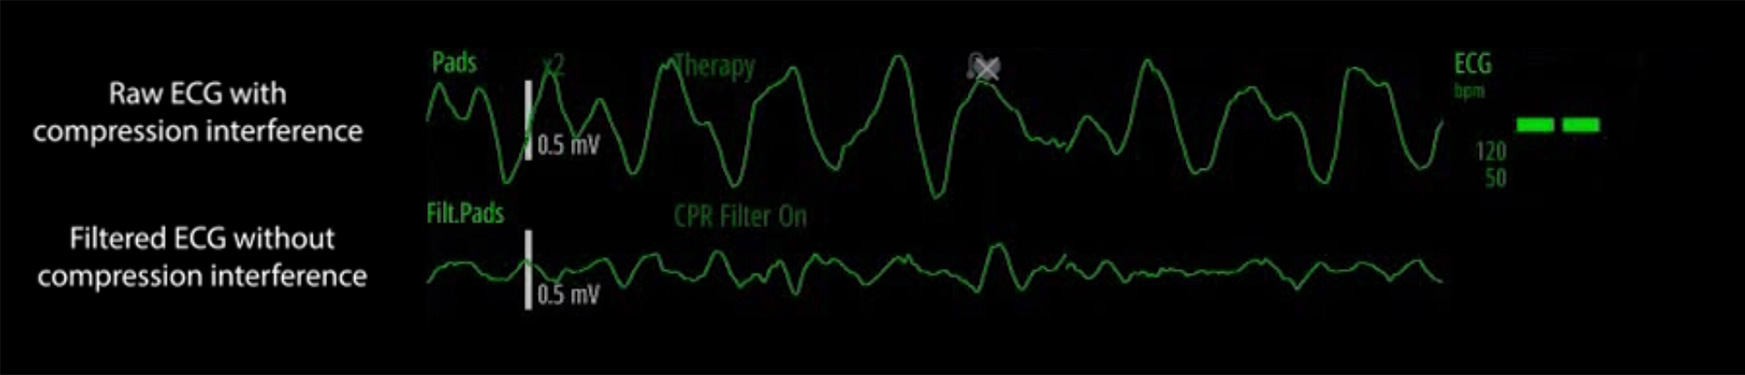

360J DesfibrilaciÃģn manual/DEA/EstimulaciÃģn/Monitoreo: ECG, SPO2, TANI, CO2

AlarmSight™ Visual

Soporte para la resoluciÃģn de problemas con visualizaciÃģn grÃĄfica